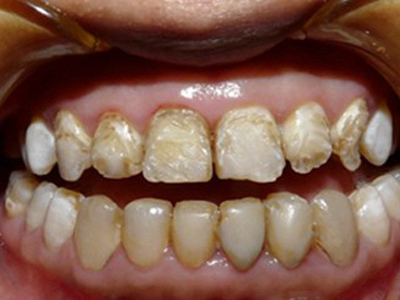

牙釉质发育不全牙齿有条纹凹陷图

牙釉质发育不全患者牙齿上出现棕褐色的条纹凹陷,部分融合成一小片,牙齿整体发白,形态较完整,患者无明显疼痛、流血等异常表现。

牙釉质发育不全牙齿上棕色的坑图

牙釉质发育不全程度严重时,牙齿上出现较深的条状、点状凹陷,内含深褐色物质,并且牙齿尖端的牙釉质缺失,牙齿变得相对脆弱。

牙釉质发育不全牙齿棕色有缺损图

牙釉质发育不全患者牙齿出现明显的缺损表现,并于表面形成深褐色的蜂窝状、竖条状的凹坑,甚至形成洞,患者上下牙失去咬合能力。